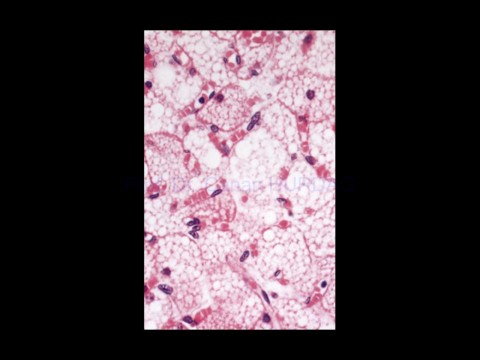

Page 58 - EPİDEL DOKU II

Prof. Dr. Canan HURDAG

H&E X 320